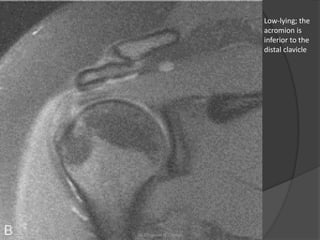

Low-lying; the

acromion is

inferior to the

distal clavicle